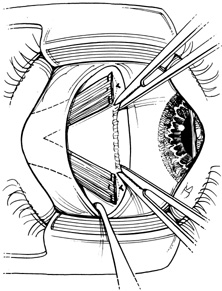

Step 1. The lateral rectus muscle is isolated through either a limbal (Fig. 1) or fornix incision. The muscle is dissected free of intermuscular septum and check ligaments for a distance of approximately 15 mm posterior to its insertion. When a fornix approach is used, the procedure can be performed through a single inferior temporal incision; however, making a second superior temporal fornix incision facilitates reattachment of the superior arm of the muscle.

Fig. 1. The lateral rectus muscle is isolated through a limbal incision and dissected free of intermuscular septum and check ligaments for a distance of approximately 15 mm posterior to its insertion.